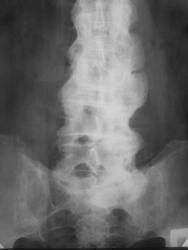

Скованность позвоночника, ограничение подвижности позвоночника. Ваше мнение?

Немного сомневаюсь, но что то крестцово подвздошные сочленеия слабо изменены, справа просматривается даже не в стандартной укладке, да и дугоотростчастый сустав просматривается справа в сегментеL4-5, с чего бы он сохранился при таком распространеиии... Есть над чем подумать. А так, с первого взгяда очень даже похоже.

Классно "похулиганили", теперь то уж точно не поверю, что Бехтерева...это опять Форестье...

В поясничном отделе наверно деформирующий спондилёз.

Надо подумать о ревматизме. А сколько лет представителю снимка?